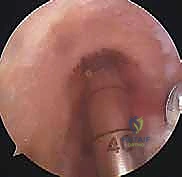

الخطوة الأولى: الفحص بالمنظار الجراحي 4K

يستخدم الدكتور